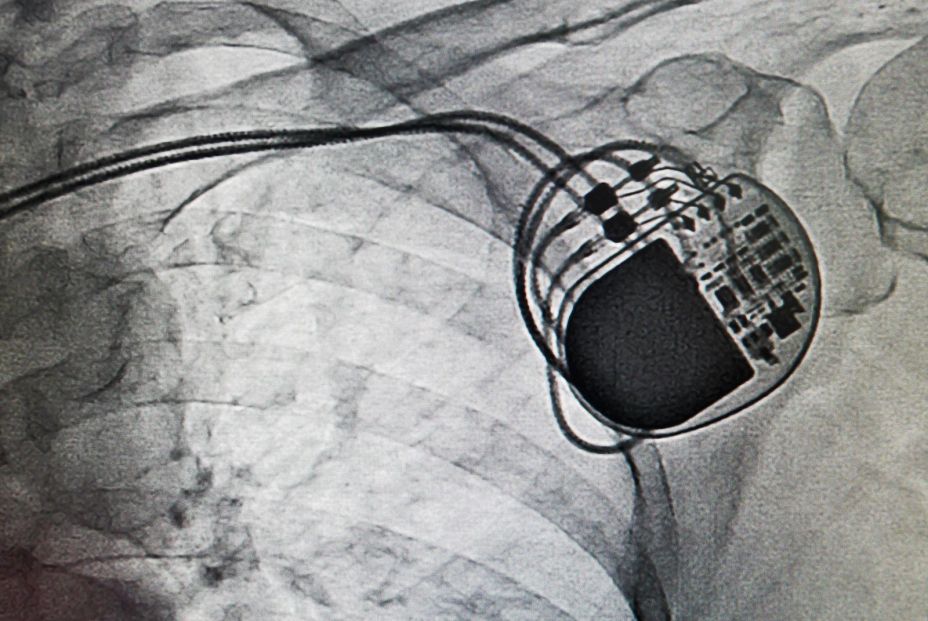

Dispositivos cardíacos

Los dispositivos cardiacos implantables mantienen la función cardiaca. Los más frecuentes son los marcapasos, desfibriladores automáticos implantables (DAI) y sistemas de resincronización cardíaca y, en menos casos, catéteres o electrodos intracardiacos, válvulas protésicas y dispositivos de cierre.

"Son herramientas vitales para muchos pacientes, pero, como todo material implantado, conllevan un riesgo potencial de infección", ha indicado María Sánchez, del Servicio de Medicina Interna del Complejo Hospitalario de Salamanca.

Los síntomas más comunes en las infecciones por dispositivos cardíacos son fiebre persistente sin causa aparente, rojez, dolor o secreción en la zona del generador, y, en casos avanzados, sepsis o bacteriemia. Ante la sospecha diagnóstica, el ecocardiograma detecta vegetaciones o abscesos; los cultivos confirman la infección bacteriana y el PET-TAC confirma diagnósticos dudosos y delimita la extensión de la infección.

Más del 70% de los casos se deben a cocos grampositivos, sobre todo 'Staphylococcus aureus' y 'S. epidermidis', bacterias de la piel que se adhieren a los dispositivos y forman biopelículas o biofilms que dificultan la erradicación con antibióticos. Otros microorganismos menos típicos son los enterococos, bacilos gramnegativos y, en pacientes inmunodeprimidos, los hongos.

Los factores de riesgo incluyen diabetes mellitus, insuficiencia renal crónica, inmunosupresión, cirugías largas o repetidas, y reintervenciones en el mismo bolsillo del dispositivo o una bacteriemia; condiciones locales (hematomas, seromas o heridas quirúrgicas) y el uso inadecuado de profilaxis antibiótica.

"El tratamiento solo antibiótico rara vez es suficiente; en la mayoría de los casos es imprescindible retirar todo el sistema, generador y electrodos, para eliminar biopelículas resistentes. Solo en infecciones superficiales muy precoces puede intentarse un manejo conservador bajo estrecha vigilancia", explica Sánchez.

El tratamiento de la infección del dispositivo conlleva la retirada del mismo y el inicio del tratamiento antibiótico cuya duración dependerá de la gravedad y extensión de la gravedad, se espera entre 7 y 14 días para reimplantarlo. El nuevo dispositivo se coloca en el lado contrario o se opta por sistemas sin cables (leadless pacemakers), para reducir el riesgo de reinfección; a los pacientes que dependen de marcapasos se les implantan hasta el dispositivo definitivo marcapasos transitorios o temporalmente, en pacientes que precisen desfibirladores se puede optar por chalecos desfibriladores.